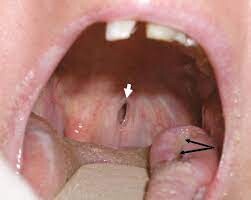

Vasculitis can affect all parts of the body and the mouth is no exception. Large, persistent and excruciatingly painful mouth ulcers are sometimes a characteristic of active Wegener’s Granulomatosis as is severe toothache that moves around the mouth, especially in the upper jaw.